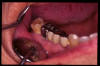

CM Falta de contactos interoclusales

CM Extrusión de incisivos inferiores por falta de contactos oclusales